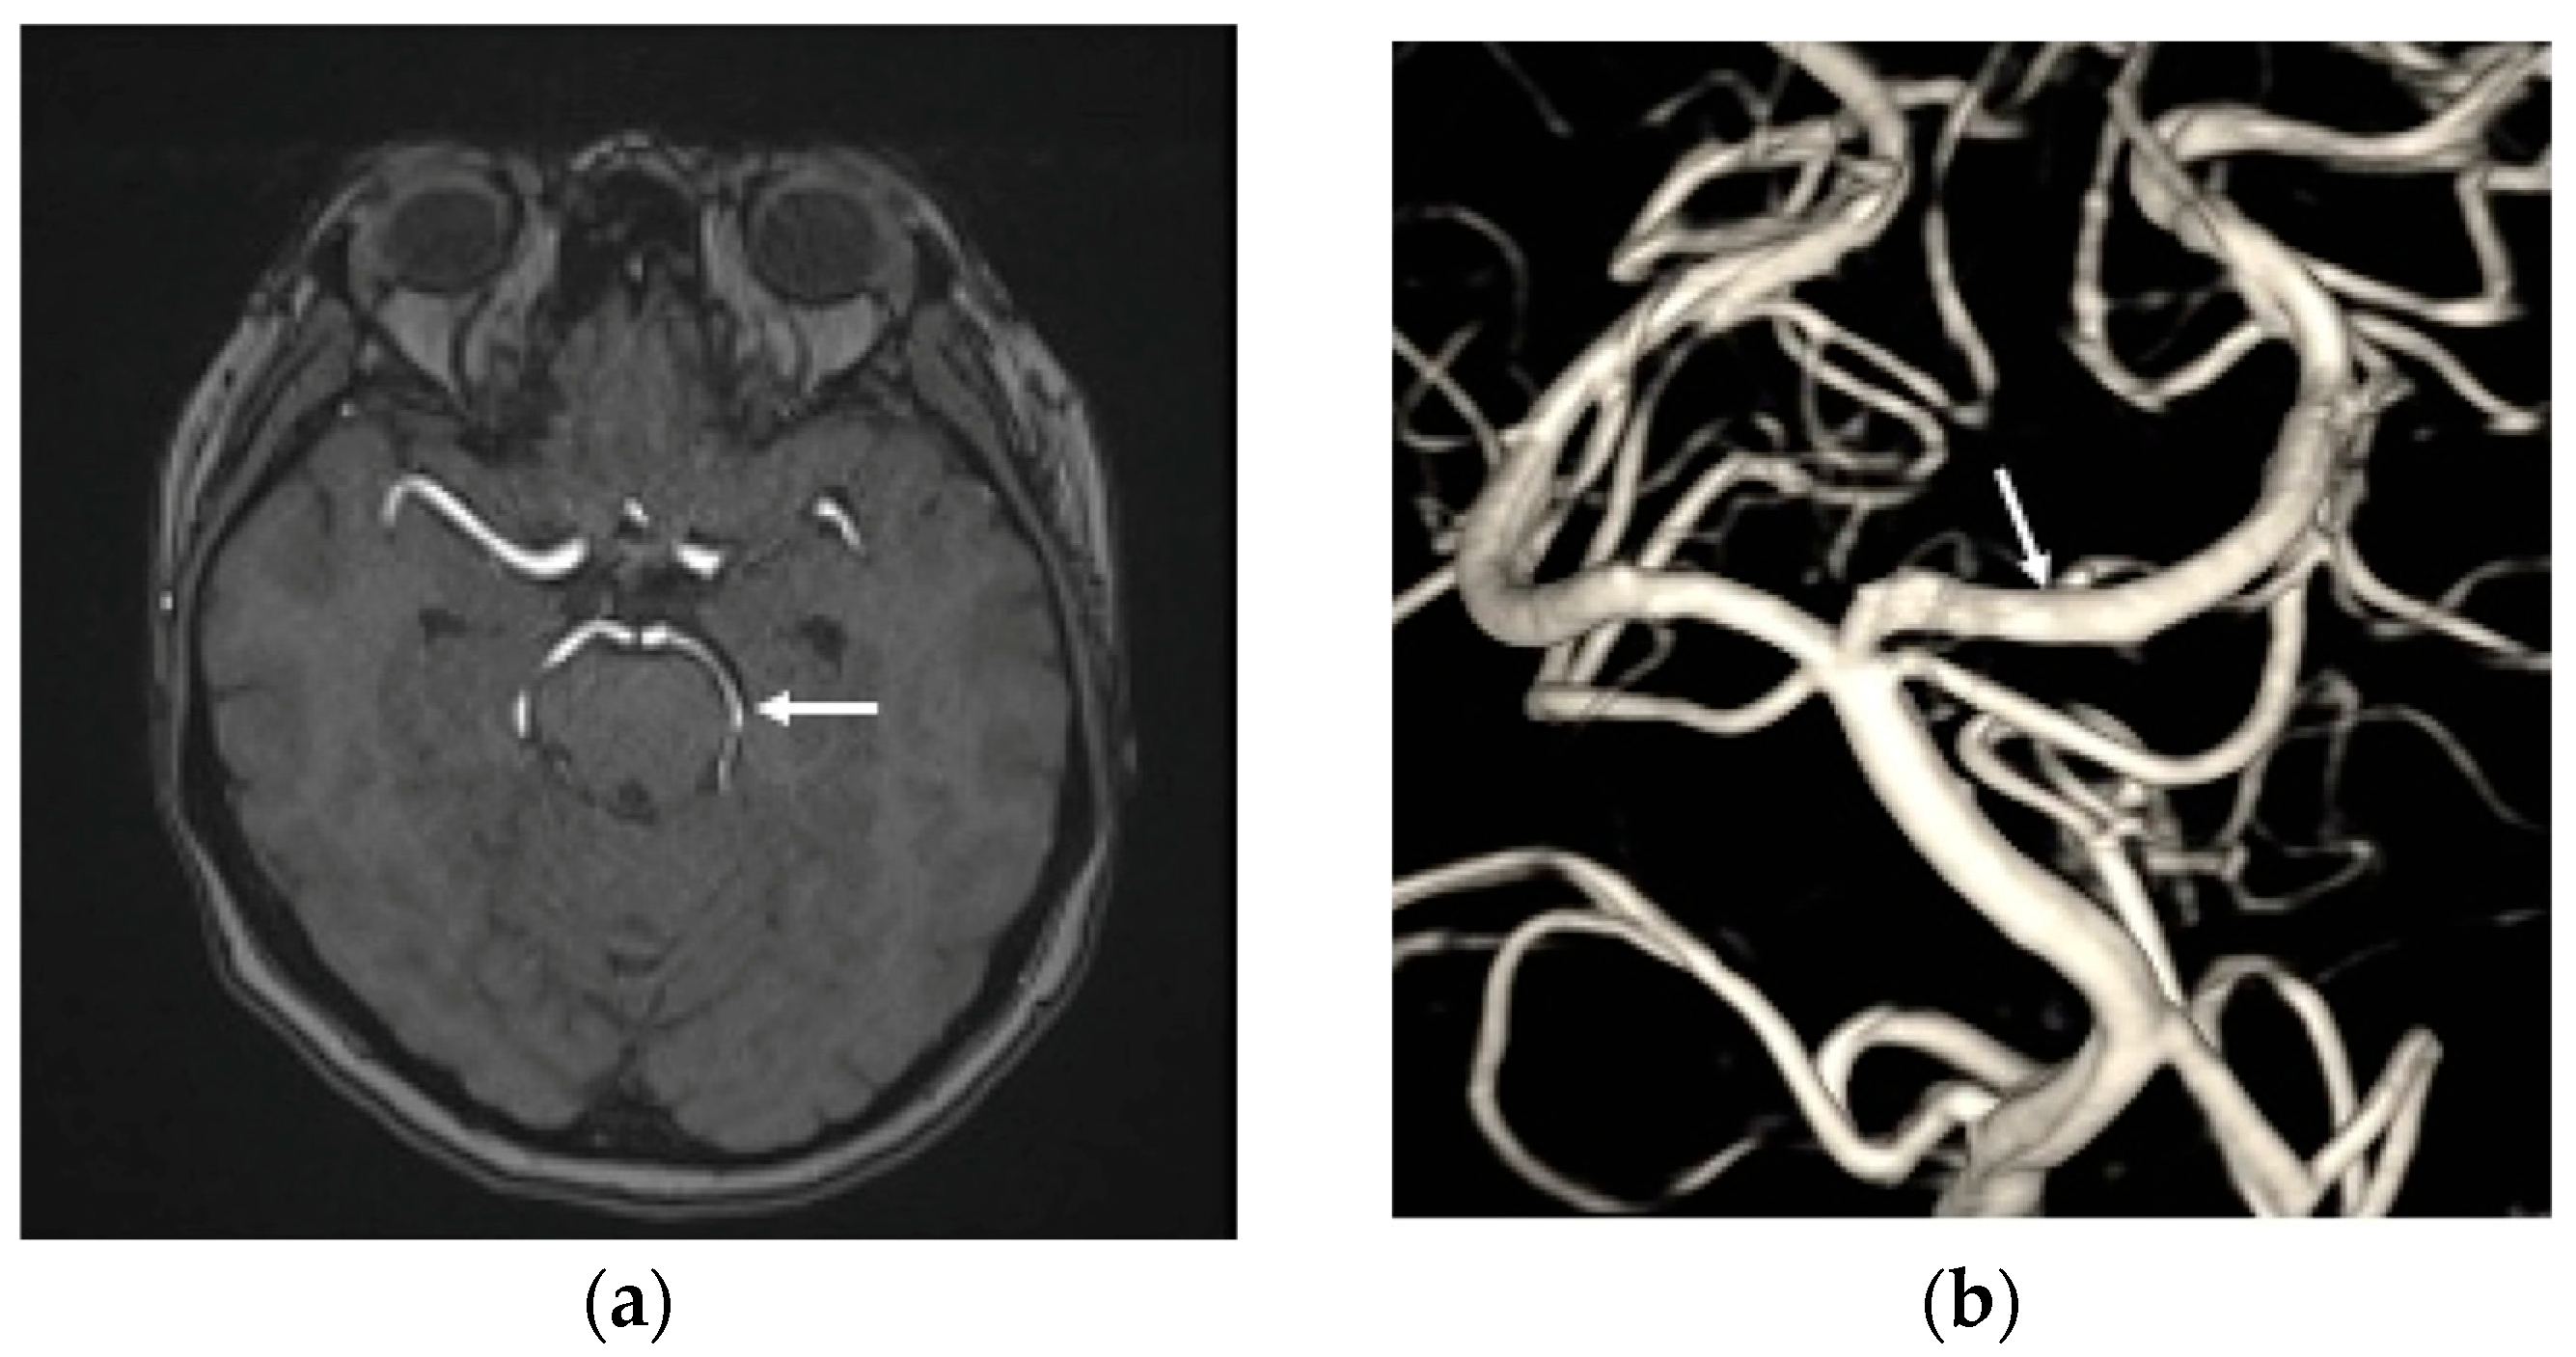

The patient was maintained on clopidogrel 75 mg daily for one year, with scheduled follow-up imaging that included brain MRI with MRA at three months and one year, as well as a DSA after TAE at six months. These studies were obtained to evaluate interval changes in the configuration of the left PCA aneurysm and to monitor for potential thromboembolic events or in-stent thrombosis following the endovascular procedure. Follow-up brain MRA demonstrated a patent left PCA without evidence of thromboembolism (Figure 4a). The six-month DSA confirmed complete and durable occlusion of the dissection aneurysm, without recurrence or parent artery stenosis (Figure 4b). The patient was discharged approximately one month after the SAH and subsequently recovered well following both the TAE and MISS. At the one-year follow-up, she had a Barthel Index score of 100, and a mRS score of 0, indicating full function independence.

Figure 4.

(a) The time-of-flight magnetic resonance angiography revealed the left PCA patency (white arrow head) without thromboembolic events post transarterial endovascular treatment (TAE) three months; (b) the DSA at six months after TAE shows that the left PCA P2 dissection aneurysm has achieved total obliteration, with no stenosis observed in the parent artery (white arrow head).